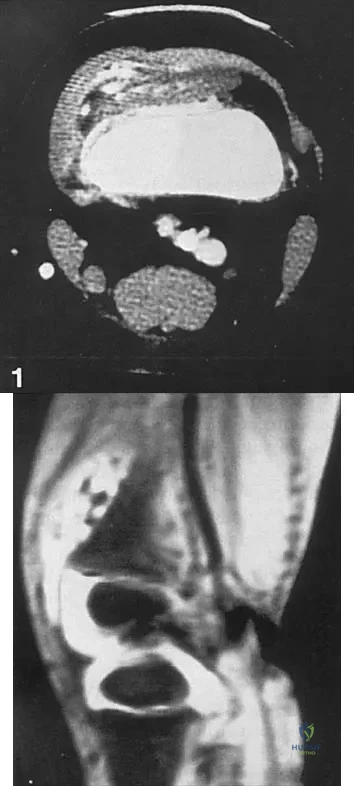

A 58-year-old man with type 1 diabetes mellitus is seen in the emergency department and he reports a 3-day history of a red swollen foot but no history of trauma. Examination reveals that the skin is intact, and the patient has discomfort with passive range of motion at the ankle, hindfoot, and midfoot joints. He denies any fever. Laboratory studies show a WBC count of 7,800/mm3, an erythrocyte sedimentation rate of 40 mm/h, a C-reactive protein level of 23, and a serum glucose of 100. A radiograph and MRI scans are shown in Figures 16a through 16c. What is the next most appropriate step in management?

Explanation